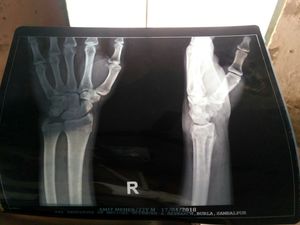

what type of fracture is this?

Mislabeled as right

That’s the LT hand

Radius head fracture

Distal radius fractures